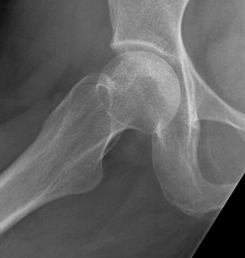

Crescent Sign

- subchondral collapse of the necrotic segment

- separation of subchondral plate from necrotic cancellous bone

Flattening femoral head Crescent sign |

Subchondral fracture IIIA: <2mm flattening IIIB: > 2 mm flattening |

Stage III: collapse / flattening femoral head with preserved joint space

Stage IV: Collapse with osteoarthritis